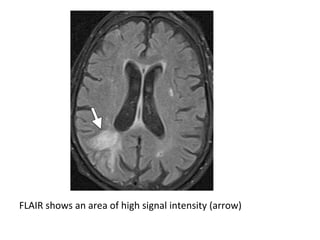

T1 shows an area of low signal intensity (arrow)

T2 shows an area of high signal intensity (arrow)

FLAIR shows an area of high signal intensity (arrow)